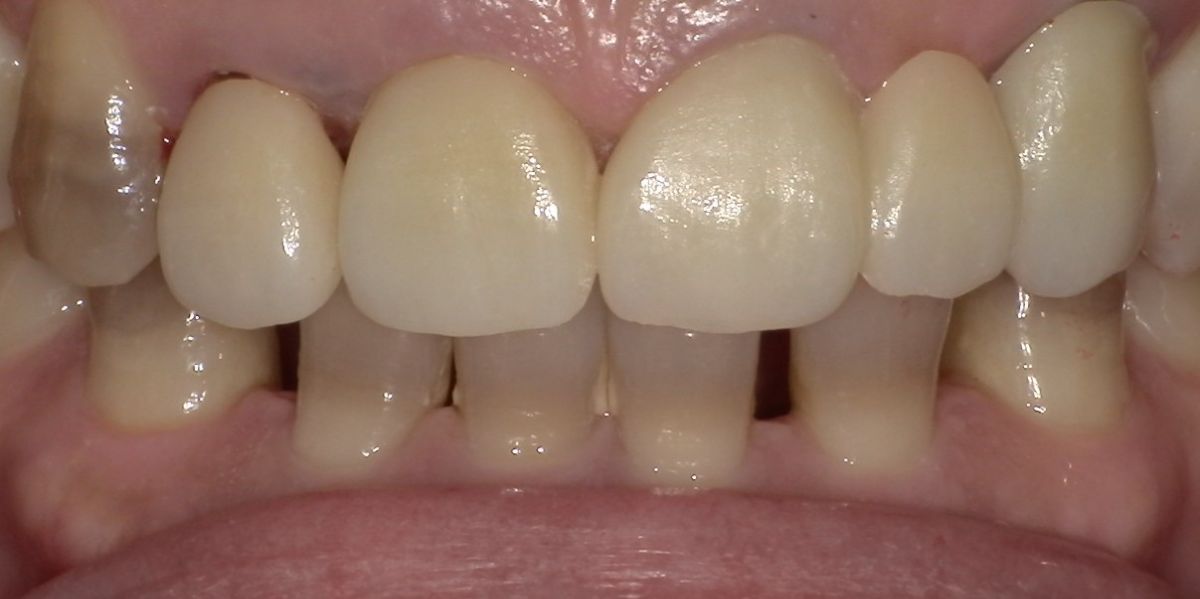

<治療前>

-

<治療後>

主訴:上の前歯の色が気になる、もっと白くしたい

上部構造:すべてジルコニアセラミック

費用:¥1,320,000

治療期間:2ヶ月

副作用・リスク:特に前歯部は、色合わせのために何度か作り替えが必要な場合があります。歯周病、う蝕、根の治療が必要な場合はさらに時間がかかります。